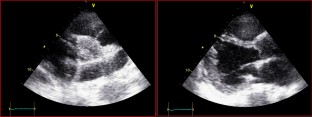

Fig. 3